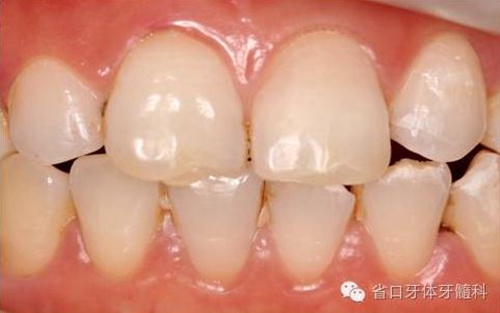

圖16. 術(shù)后口內(nèi)照

圖18. 術(shù)后23天隨訪的口內(nèi)照片